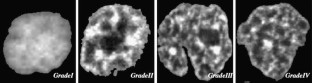

Fig. 1